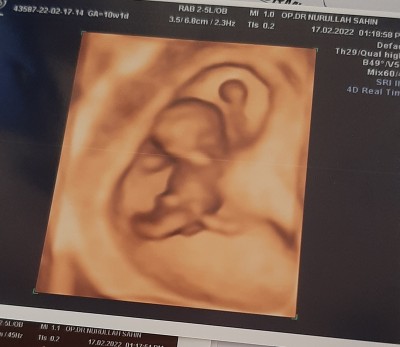

tahminde bulunabilir misiniz ❤

Gebelik haftası 10

3 aylık bile değil kız ama orda çıkıntı gibi bişey gözüküyor pipi olabilir mi acaba bilemedim senin içinden ne geçiyor cinsiyet:)

O kordonmuş doktorum dedi ilk bebeğim erkek buda kız olsun istedik ama sağlıklı olsun tabi içimden de kız gibi geçiyo ama bilemedim :)❤